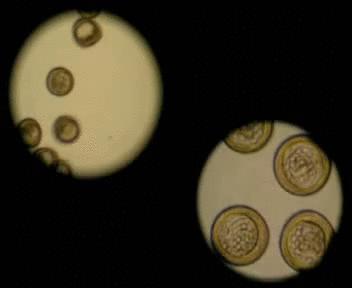

The potency of the synthesized compounds targeting microtubules was further assessed using sea urchin embryos, as well as a panel of human cancer cells from breast adenocarcinoma, melanoma, ovarian and lung tumors. Sea urchin embryos have been shown by the team to be a good model to study specific tubulin-binding agents. They cause embryos to rapidly rotate, as opposed to moving in the ordinary way (cf. the left and right sides of the animation). This effect can be easily observed using a light microscope enabling the scientists to evaluate the anticancer potential of a compound within a short amount of time. Moreover, the team found sea urchin embryos to be more sensitive toward the identified agents than cancer cells. A difference between the duration of the mitotic cycles of sea urchin embryos and cancer cells (40 minutes vs. 24 hours) may lead to distinct effects of the small molecules on tubulin dynamics and could thus account for this phenomenon.The molecule featuring 3-thiophene- and para-methoxyphenyl substituents was identified to be the most potent anticancer agent in the studies. According to the researchers, it is this combination of functional groups, as well as the unique topology of the molecule that are responsible for its unique activity. Specifically, the new agent displays antitubulin properties as it blocks cell division by affecting microtubules and thus can destroy the chemoresistant cells of ovarian carcinoma.